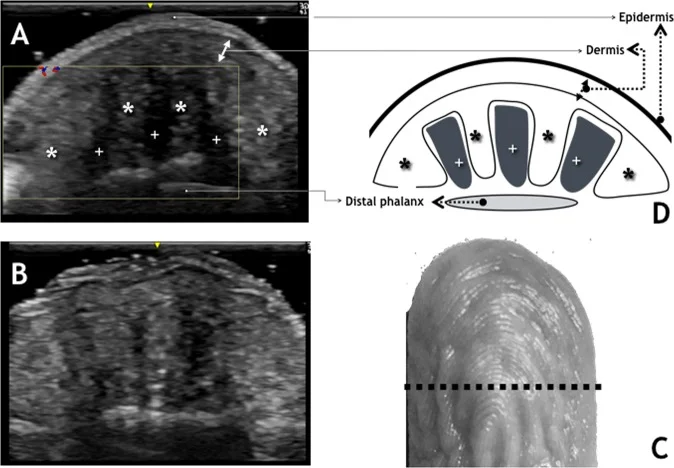

2019年发表在《Scientific Reports》上的超声研究提供了直接证据:泡水起皱后,手指末端低回声区(代表富含液体的组织空间)面积减少了约50%——从占总横截面积的12.9%降至6.6%。

图片来源: Scientific Reports / PMC - 手指末端超声图像,显示起皱前(A)后(B)的组织结构变化